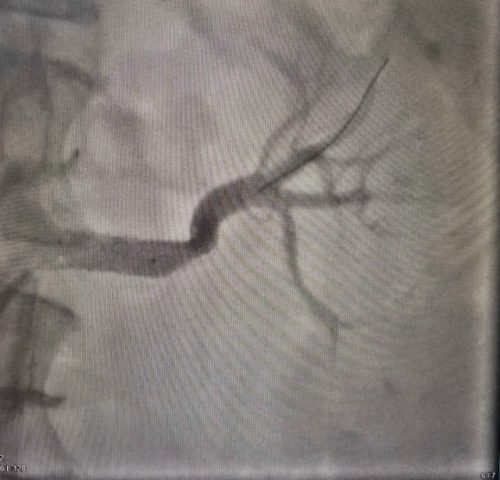

Женщину перевели в областную больницу №1, где выполнили ангиографию (контрастное исследование) почечных артерий. Результаты показали стеноз – сужение до 80%. Тогда пациентке сделали балонную ангиопластику и стентирование артерии – «расширили» артерию и установили стент. Операцию провели под руководством врача отделения рентгенхирургических методов диагностики и лечения Ивана Тимошина. Давление горожанки наконец пришло в норму, что позволило сократить количество лекарств.